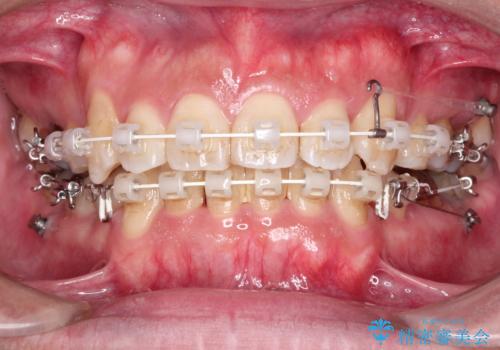

- 審美装置(ブラケット:白/ワイヤー:白)

- 2年3ヶ月

- 10-30回